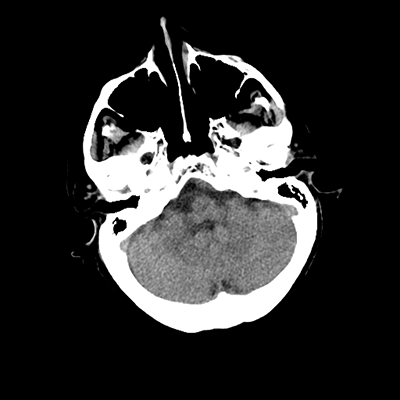

An 76 year-old man with HTN, CAD s/p PCI (two years prior), and PAD initially presented to the ED with subacute left hemiparesis and gait difficulties. He was found to have a large right frontal tumor. He was admitted to the NCCU, and then undergoes a craniotomy for tumor resection later in the week. A post-op head CT is obtained.

There are expected post-operative changes, along with some scant hemorrhaging along the posterior and inferior aspects of the surgical bed. We'll want to ensure that this hemorrhage is stable with a repeat scan, at which point we can start DVT chemoprophylaxis-- will end up being between 24-48 hours post-op.